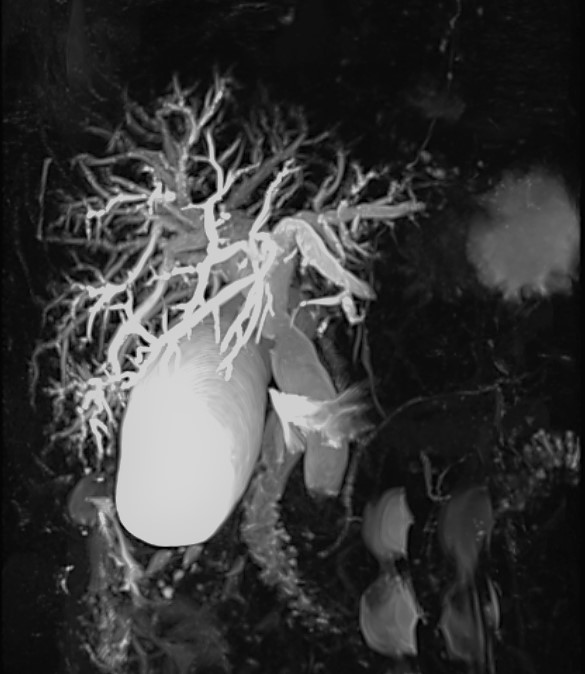

BILI-IRM